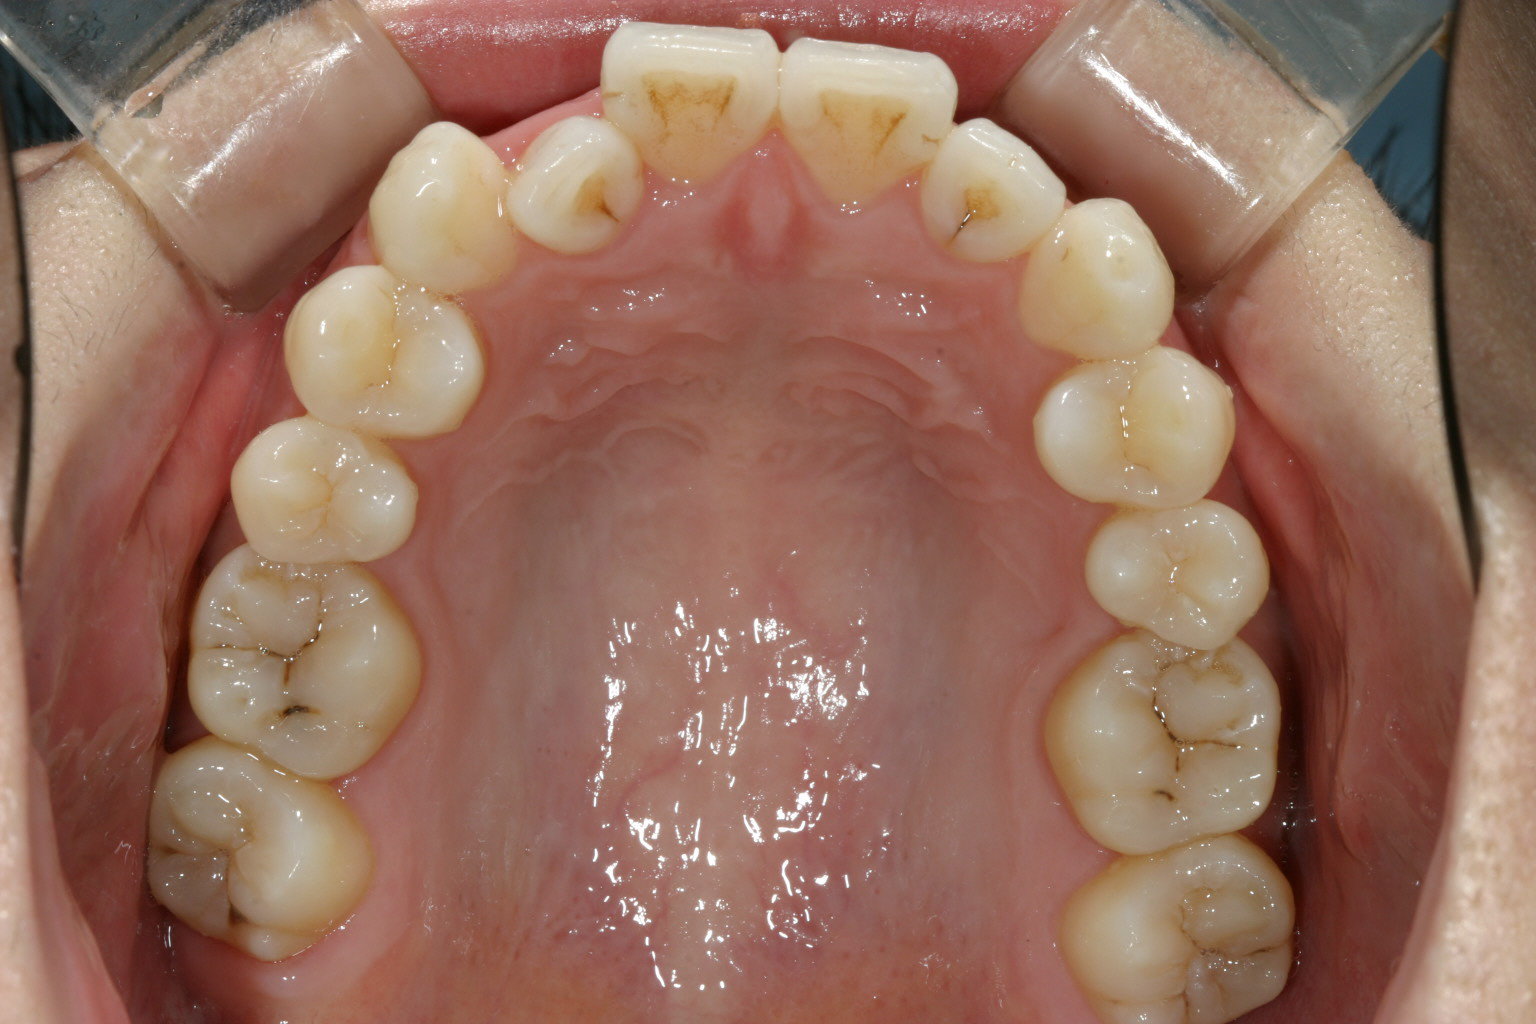

その後半年でここまで改善です。 前から見るとこんな感じです。 ここから再度インビザラインで最終調整です。

綺麗に改善しました。

下顎のガタガタも綺麗に改善しました。